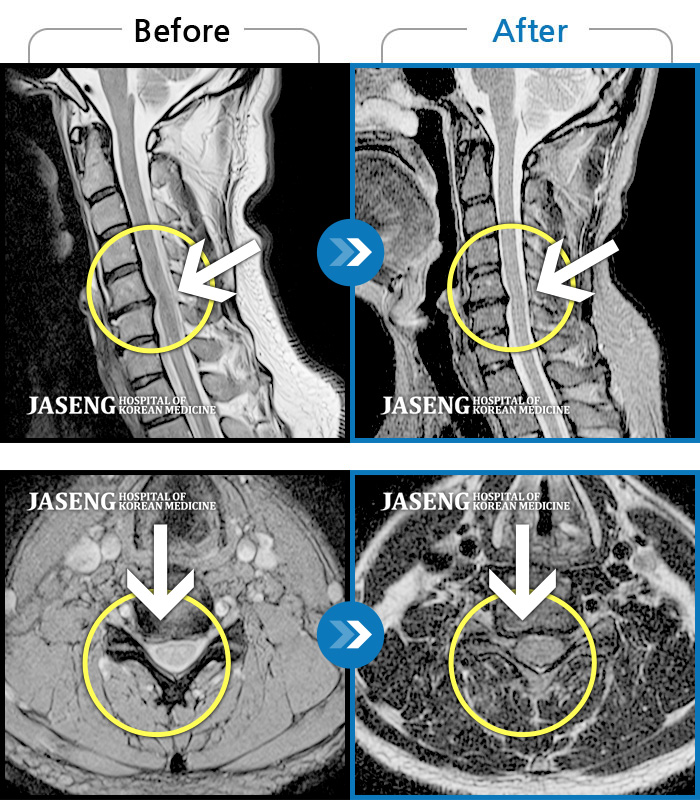

목디스크

도움받은 사례

인천 · 강아현 원장

목 통증 및 좌측 팔 저림으로 숨 쉬는 것도 불편하고 움직일 수가 없는 상태로 내원하셨습니다.

촬영시기

2023.02.13 ~ 2023.09.14

2023.09.15

조회수 110